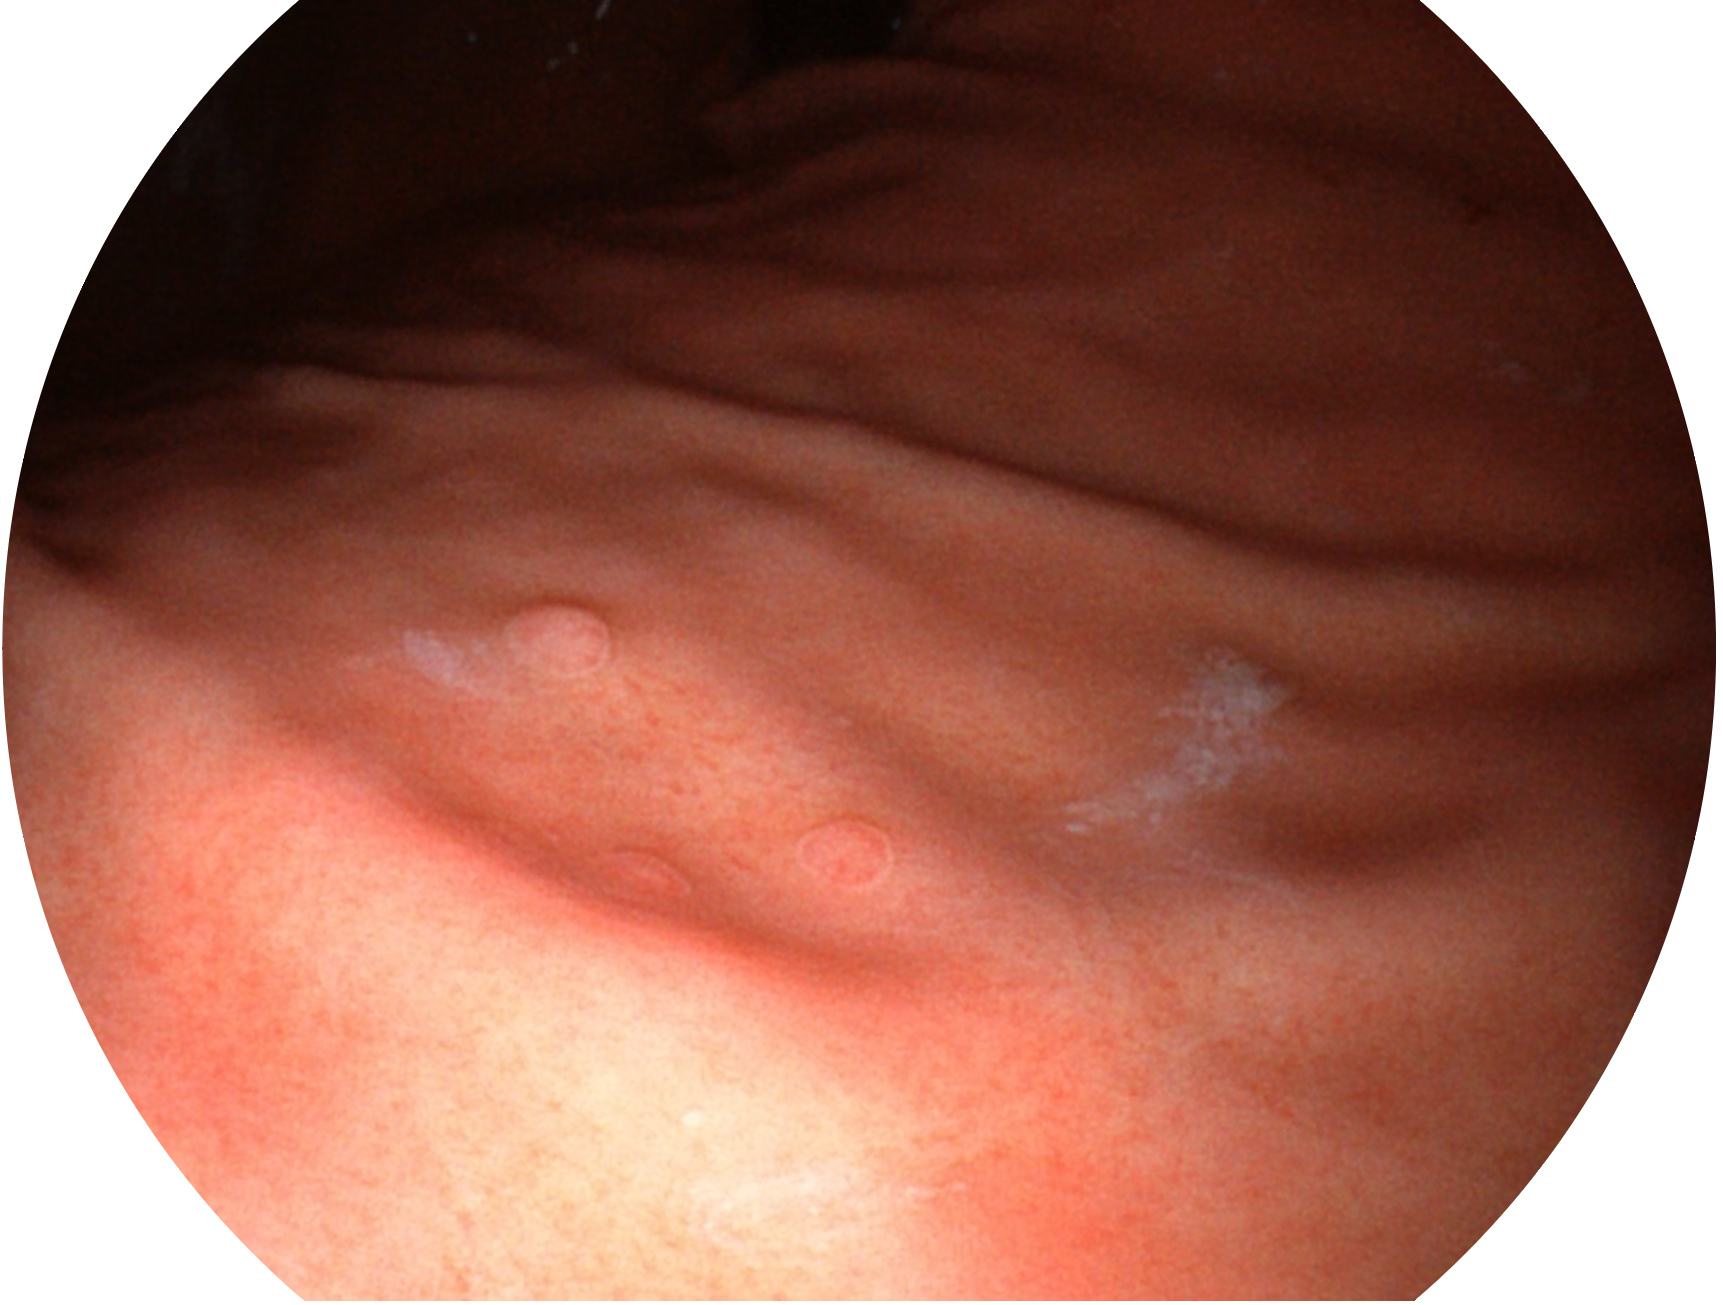

竞技宝(JJB)官方网站新开发的内镜染色技术,主要是基于多波长LED 光源的开发,VLS-55Q 四波长LED 光源是由四个不同颜色的LED光按照相应照明模式所规定的特定发光比例进行合束后形成,合束后形成的照明光的光谱由红光、绿光、蓝光及蓝紫光这四个不同的波段范围构成。具有更高光谱自由度,通过光谱比例的控制,实现了聚谱成像技术,英文全称为“Spectral Focused Imaging, SFI”,缩写为“SFI”和光电复合染色成像技术,英文全称为“Versatile Intelligent Staining Technology, VIST”,缩写为“VIST”。